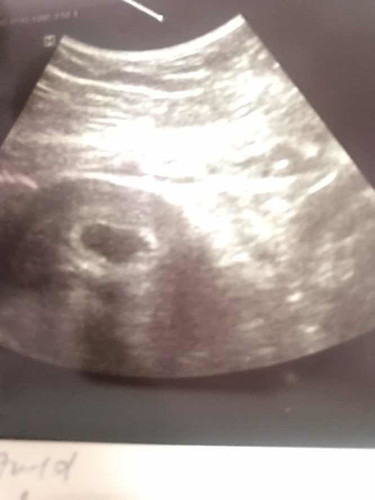

Tadi pg scan kli kedua kat kk, masa first time scan xnampak bby atau kantung, doc bg 2 mngu suh dtg blik, so alhamdulilah nampak kantung dan heartbeat bby, tapi still xdpt lagi due bersalin, mommy kat sini bole agak x rasa nya dah brpa week biasa nya?

Sy agak2 dah 9 week